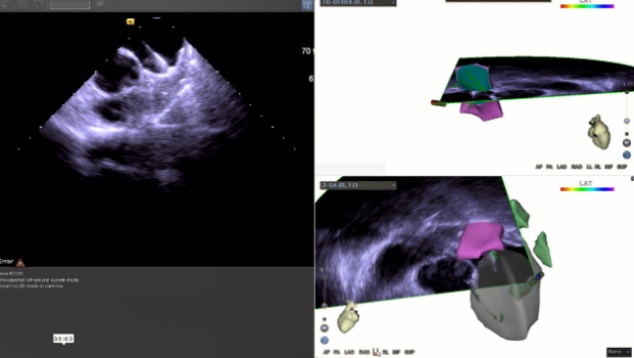

一个月后,肖方毅医师在心腔内超声和三维电解剖标测系统指导下为蔡老伯成功实行房颤射频消融联合左心耳封堵术。这是目前最新的技术,整个消融过程因为有心腔内超声的指引,无需任何射线,直视下精准构建左房模型,精准消融(图1)。消融后肖方毅医师用自己创立的“FLAVOR”术式,在腔内超声指导下顺利植入左心耳封堵器(图2,图3),避免了以往术中需要做经食道心超检查的痛苦。

图2:术中心腔内超声指导下行左心耳封堵术